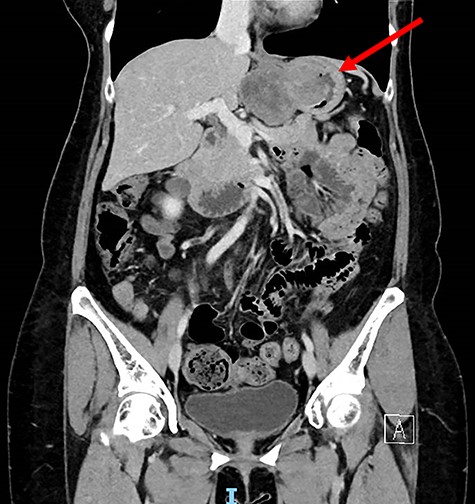

Computed tomography thorax abdomen pelvis performed showed a 4.2 × 8.0 × 5.3 cm transmural mass with prominent luminal and exophytic components at the gastric cardia and GEJ (Fig. 2). There were otherwise no enlarged lymph nodes or distant metastases.